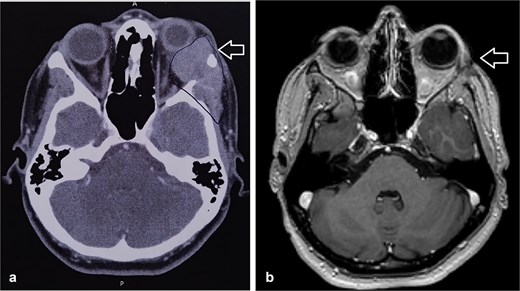

During follow-up, the patient complained of swelling at the left angle of the mandible and left lateral canthus. Orbit MRI showed local disease progression (Fig. 4). Ultrasonography of the left parotid region showed an irregular hypoechoic lesion in the left parotid gland. A PET scan revealed hypermetabolic malignant irregular soft tissue thickening within the lateral periorbital area of the left eye, consistent with a recurrence disease. Additionally, there is a new hypermetabolic irregular soft tissue mass in the left parotid gland with numerous bilateral scattered pulmonary nodules (Fig. 5). A biopsy from the left parotid gland confirmed the diagnosis of ACC, aligning with the primary tumor. The patient was diagnosed with lacrimal gland ACC with metastasis to the left parotid gland and the lungs. The Head and Neck multidisciplinary team proceeded with systemic chemotherapy using cisplatin and Navelbine. The patient started chemotherapy with good tolerance and clinical response and is now on regular follow-up with the oncology clinic.

Orbit MRI showed a lobulated, well-defined lesion, hyperintense to intermediate on T2W (b) and hypointense on T1W (a) structures with cystic changes, measuring 2.3 × 1.9 cm and 2.6 × 1.6 cm, compared with the previous study, the lesions have increased in size.

MRI is the preferred modality to detect bony invasion and perineural spread. ACC usually appears as T1 isointense and T2 hyperintense with enhancement . Our patient's orbit MRI showed a lobulated, well-defined lesion, hyperintense to intermediate on T2W and hypointense on T1W structures with cystic changes.